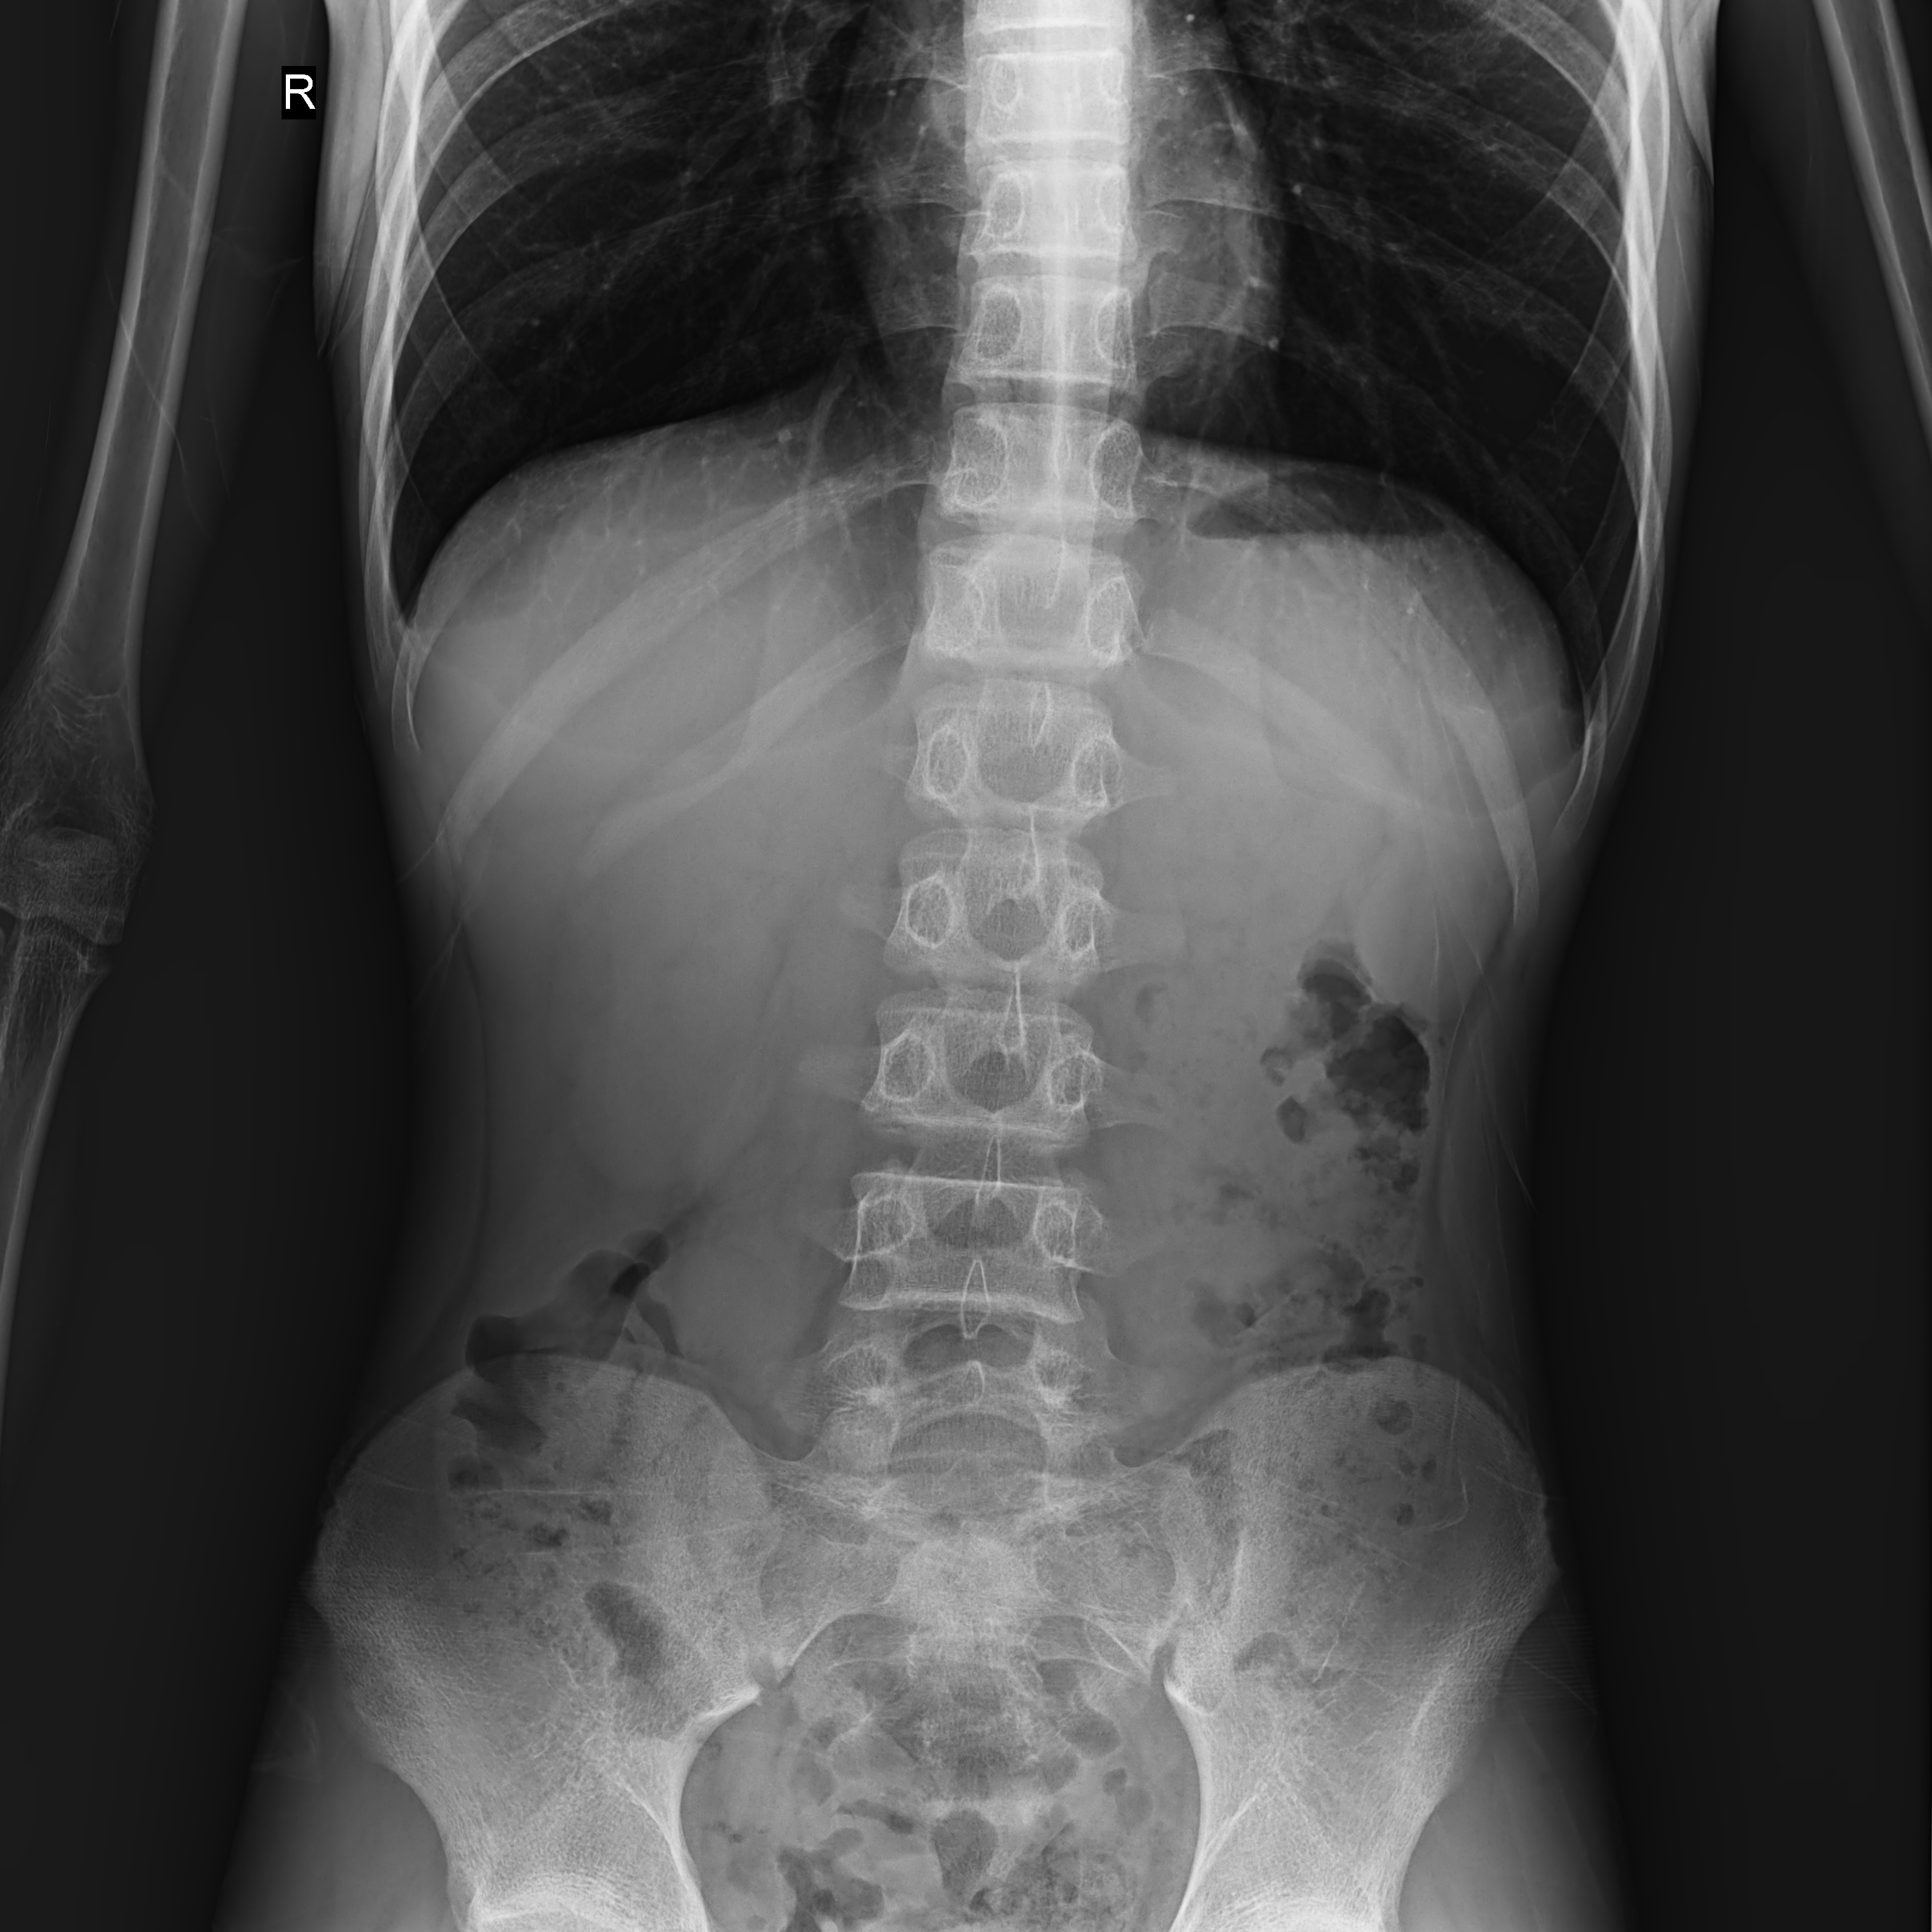

临床图片

高千伏摄影

臀